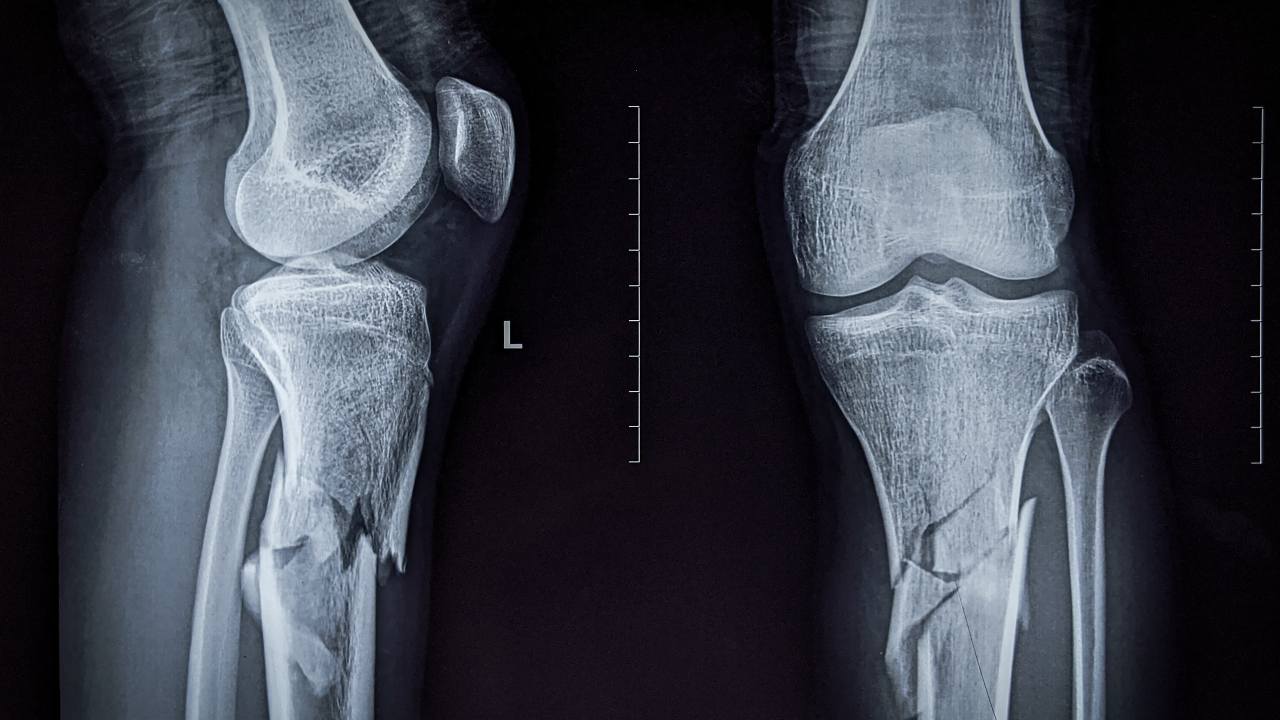

La levotiroxina y densidad ósea son dos conceptos que cada vez se relacionan más en la medicina actual. La densidad mineral ósea (DMO) es la medida que usamos para saber cuánta “materia” mineral tiene un hueso. Cuanto más baja, más fragilidad y mayor riesgo de fracturas. Por eso de pequeños nos aconsejaban tomar leche para “tener huesos fuertes”. Tener una baja densidad se asocia con la osteoporosis. Es decir, se van formando huesos más porosos y con riesgo de fractura.

El medicamento, recetado ampliamente para el hipotiroidismo, busca regular el nivel hormonal. La levotiroxina ha salvado millones de vidas. Sin embargo, parece tener un efecto inesperado en la salud de tus huesos. Estudios recientes sugieren que su uso prolongado puede contribuir a la pérdida ósea. Lo que lleva a un aumento del riesgo de fracturas, especialmente en personas mayores.

Imagen: ©Shutterstock / Susmit Das